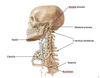

name the bony landmarks:

which cervical vertebrae are considered “typical” ?

C3-C6

C1 is also called?

it participates in what 2 major joints?

Atlas

atlanto-occipital joint (w. occipital condyles of cranium)

atlanto-axial joint (w. axis [C2])

C2 is also called?

it participates in what major joint?

Axis

atlanto-axian joint (w. atlas [C1])